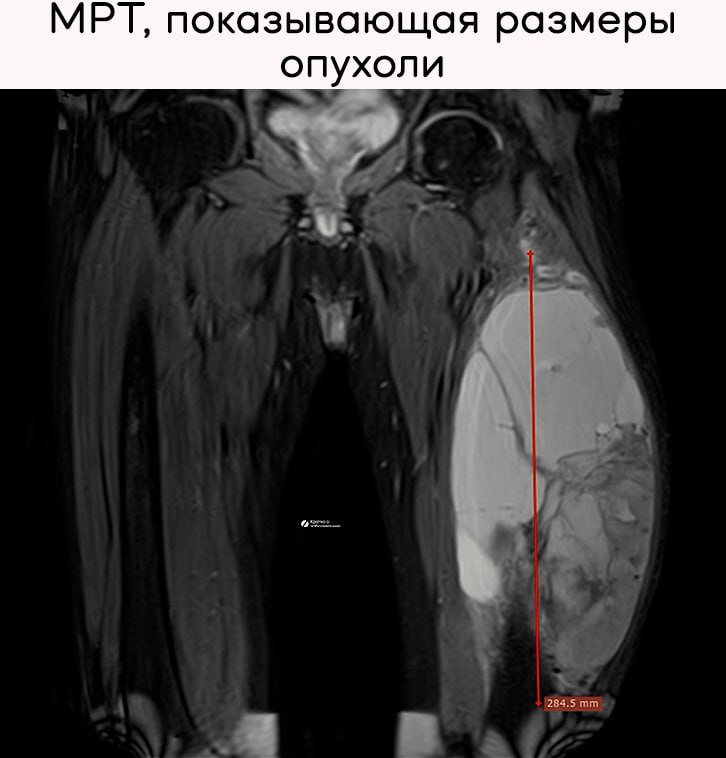

Интраоперационный взгляд на спасение конечности при объемной злокачественной опухоли четырехглавой мышцы бедра:

4 мар. 2026 г.

1.4k 7 2